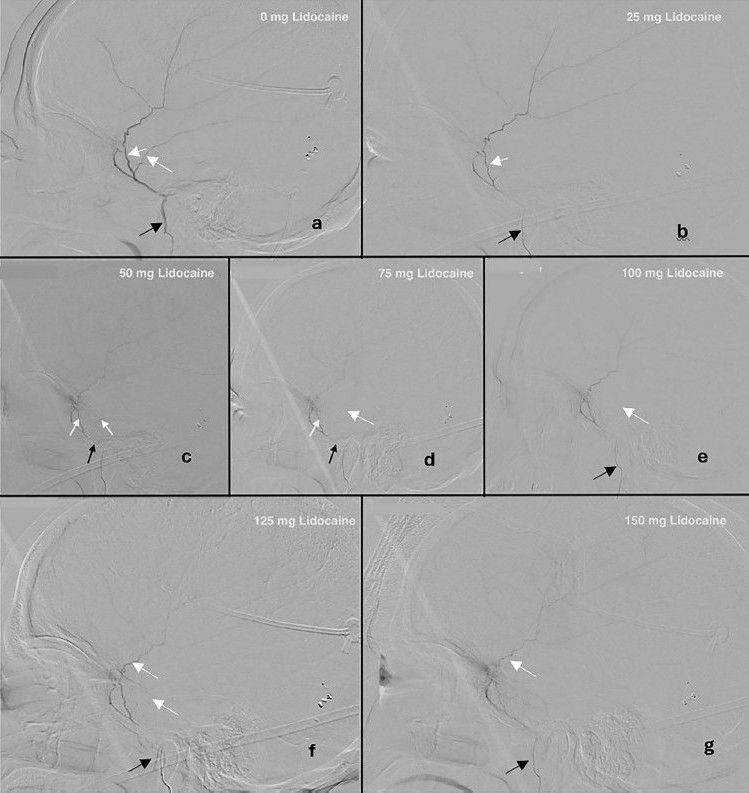

onlinelibrary.wiley.com/doi/full/10....

#neuroimaging #neurology #neuroskyence #radiology #lidocaineinfusion #middlemeningealartery #migraine

onlinelibrary.wiley.com/doi/full/10....

#neuroimaging #neurology #neuroskyence #radiology #lidocaineinfusion #middlemeningealartery #migraine